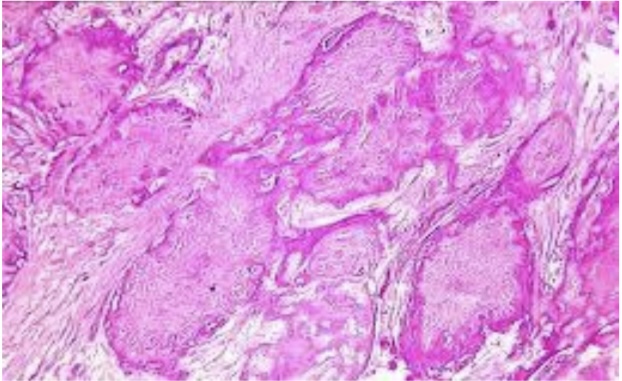

Cholesterol clefts